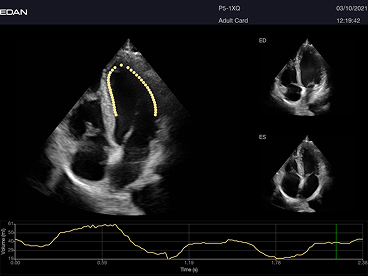

Incluye además eLV para análisis cardíaco avanzado, eOB para mediciones obstétricas automáticas y eLearn como guía interactiva.